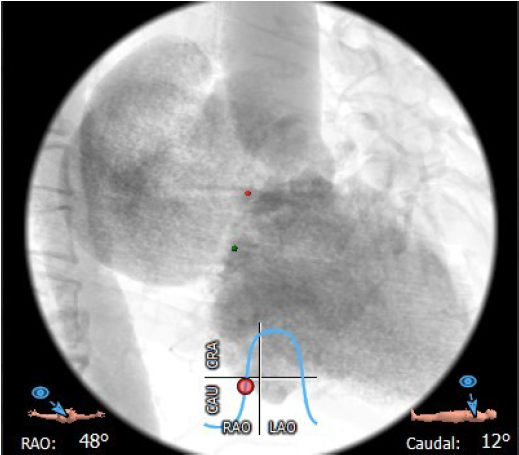

主动脉与生物瓣轴夹角76°

左室与生物瓣轴夹角145°

猪尾导管过瓣环平面进左心房

交换加硬导丝